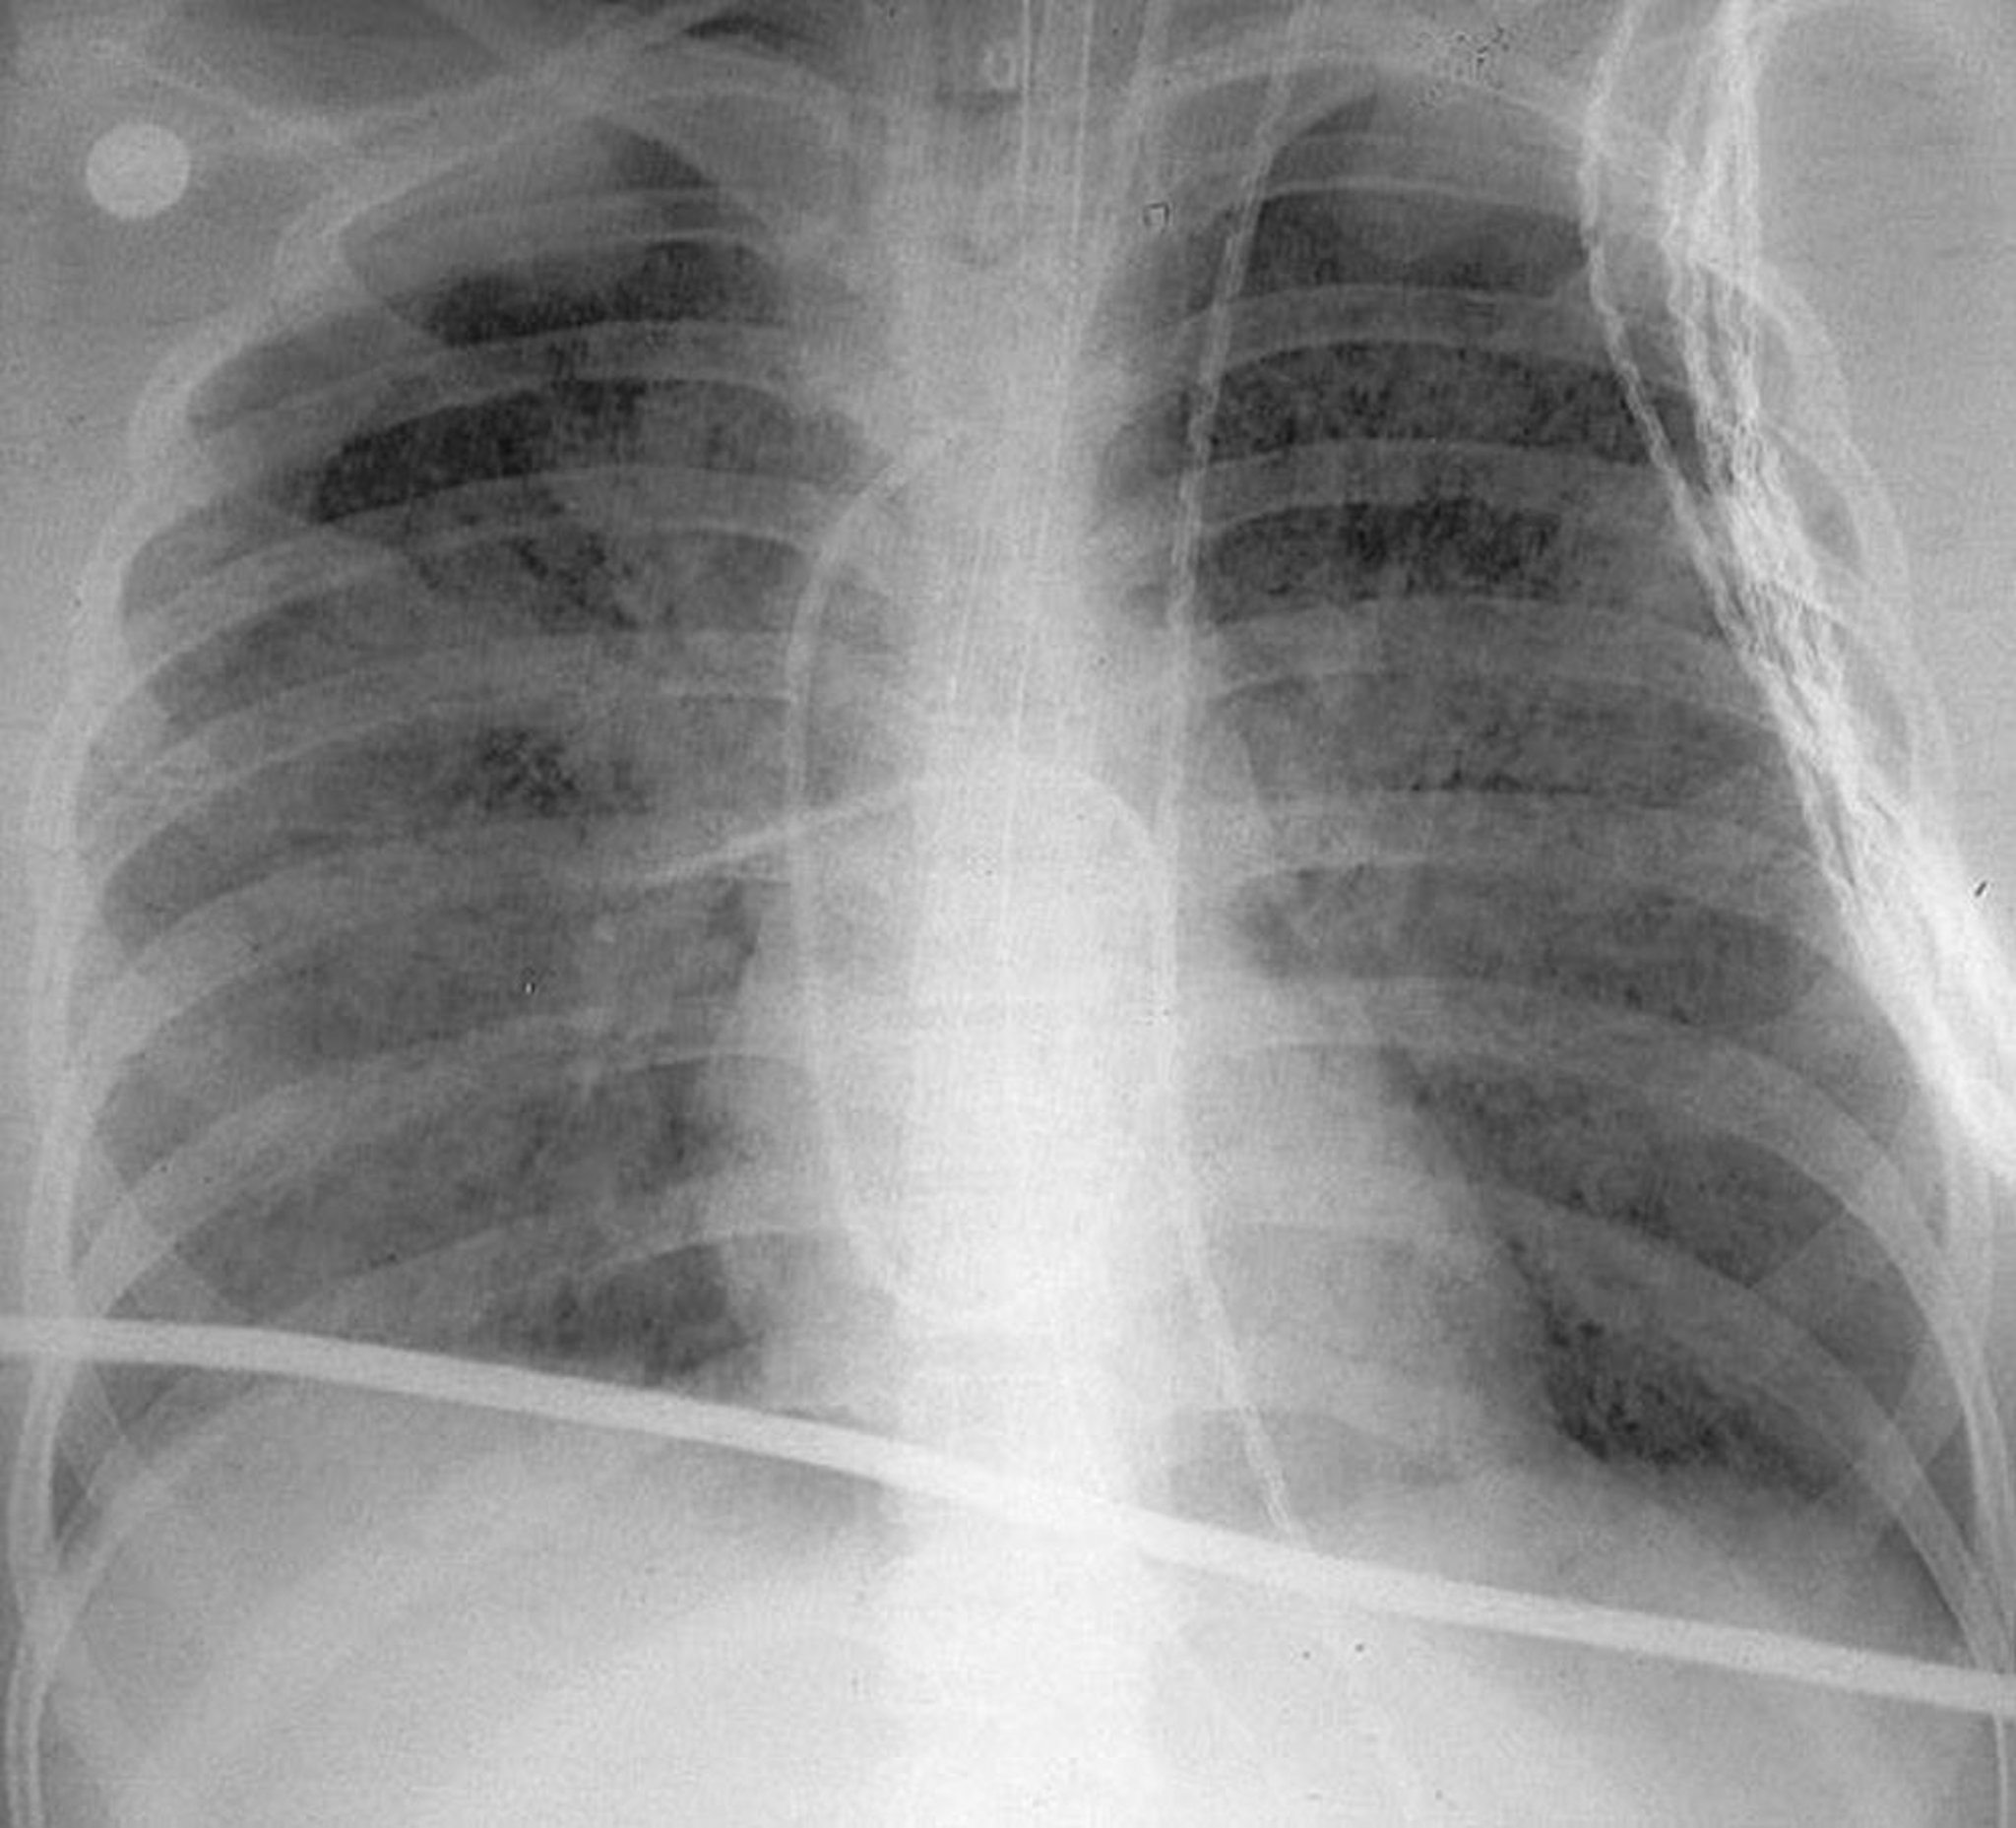

Острый респираторный дистресс-синдром

На рентгенограмме органов грудной клетки в вертикальном положении показаны диффузные двухсторонние области помутнения в легких, характерные для острого респираторного дистресс-синдрома (ОРДС).

By permission of the publisher. От Herdegen J, Bone R. In Atlas of Infectious Diseases: Pleuropulmonary and Bronchial Infections. Edited by G Mandell (series editor) and MS Simberkoff. Philadelphia, Current Medicine, 1996.